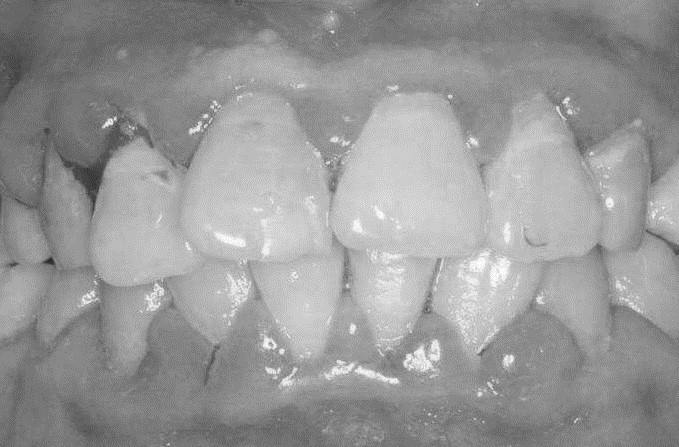

患者,女,52歲。因刷牙出血前來(lái)就診。自述刷牙時(shí)牙齦出血2年余,有時(shí)吃蘋果,饅頭等食物時(shí)牙齦出血,近1個(gè)月早晨起床偶有唾液中帶紅色血絲。曾作常規(guī)血象檢查,未見異常。無(wú)咬合不適或牙齒松動(dòng)。檢查可見全口牙石(+),有大量菌斑堆積,全口牙齦齦緣中度充血,齦乳頭充血腫大,探診出血明顯,但無(wú)附著水平喪失,牙齒無(wú)松動(dòng),咬合關(guān)系未見異常。X線片顯示全口牙槽骨無(wú)明顯吸收。檢查結(jié)果如下圖:

診斷:慢性齦炎。

診斷依據(jù):

(1)女性52歲患者,2年來(lái)刷牙咬物牙齦出血,近1個(gè)月晨起唾液中帶有血絲。

(2)曾作常規(guī)血象檢查,無(wú)異常,無(wú)咬合不適或牙齒松動(dòng)。

(3)口腔檢查:全口牙石(+),大量菌斑堆積,全口牙齦齦緣中度充血,齦乳頭紅腫,探診出血。

(4)無(wú)附著喪失,牙齒無(wú)松動(dòng),咬合關(guān)系正常。

(5)X線片顯示全口牙槽骨無(wú)明顯吸收。